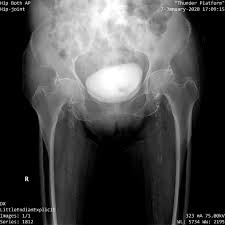

밤에 심해지는 통증

일부 고관절 질환에서는 밤에 통증이 더 심해지는 경우도 있습니다.

• 옆으로 누우면 통증 발생

• 자다가 통증으로 깸

• 특정 자세에서 통증 지속

이는 염증성 질환이나 관절 내부 압력이 높아질 때 나타날 수 있는 신호로, 단순 근육통과 구별되는 중요한 증상입니다.